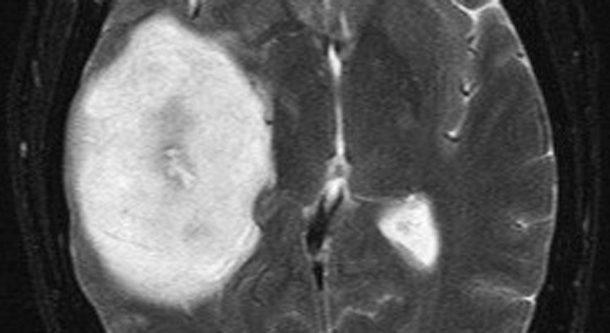

Methods: The authors identified 500 consecutive newly diagnosed patients with supratentorial GBM treated at the University of California, San Francisco between 1997 and 2009. Clinical, radiographic, and outcome parameters were measured for each case, including MR imaging-based volumetric tumor analysis.

Results: The patients had a median age of 60 years and presented with a median Karnofsky Performance Scale (KPS) score of 80. The mean clinical follow-up period was 15.3 months, and no patient was unaccounted for. All patients underwent resection followed by chemotherapy and radiation therapy. The median postoperative tumor volume was 2.3 cm(3), equating to a 96% EOR. The median overall survival was 12.2 months. Using Cox proportional hazards analysis, age, KPS score, and EOR were predictive of survival (p < 0.0001). A significant survival advantage was seen with as little as 78% EOR, and stepwise improvement in survival was evident even in the 95%-全切 EOR range. A recursive partitioning analysis validated these findings and provided additional risk stratification parameters related to age, EOR, and tumor burden.